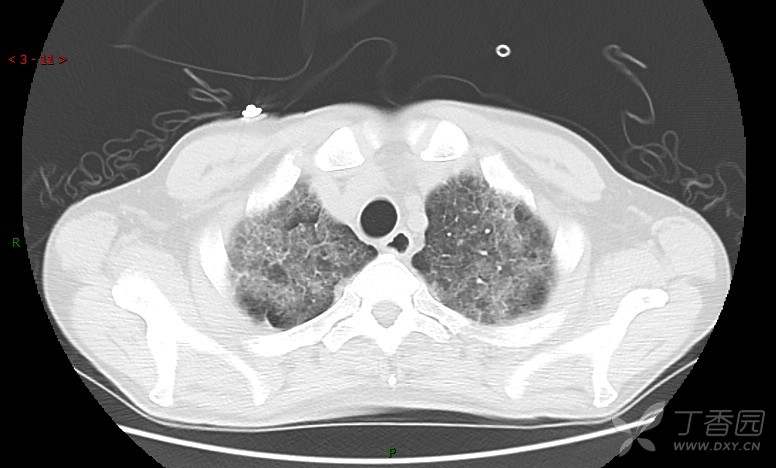

血清肿瘤相关抗原116.22U/ml↑(0--95);

癌胚抗原 61.96 ng/mL ↑ 0--5

神经特异性烯醇化酶 33.12 ng/ml ↑ 0--16.3

细胞角蛋白19片段测定 40.23 ng/ml ↑ ≤3.3

肺内弥漫性网状结节影,PET-CT却无阳性病灶,这是?(附其他2例链接)